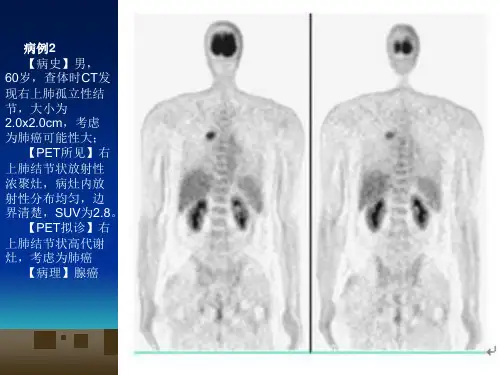

原发性肺癌

2.组织学分型:鳞癌,腺癌, 末分化细胞癌,细支气管肺泡癌,

3.放射学分型

(2)周围型:发生于段支气管及段以 下至细支气管以上

(2)周围型:实体性生长:癌细胞充满肺泡——沿 肺泡孔向周围生长——实性肿块

浸润性生长: 弥漫型:癌细胞——肺泡壁呈覆 壁生长, 肺泡充气,肺泡间隔无破坏 局灶性:病灶中心纤维结缔组织增生且 伴有炭末沉积——邻近支气管 牵拉向瘤体中心